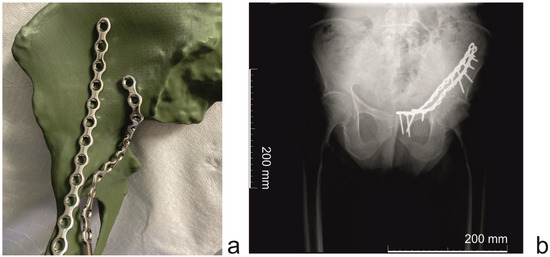

2. Materials and Methods

- Surgical plate pre-contouring;

- ○

- Sterilization of pre-contoured plates;